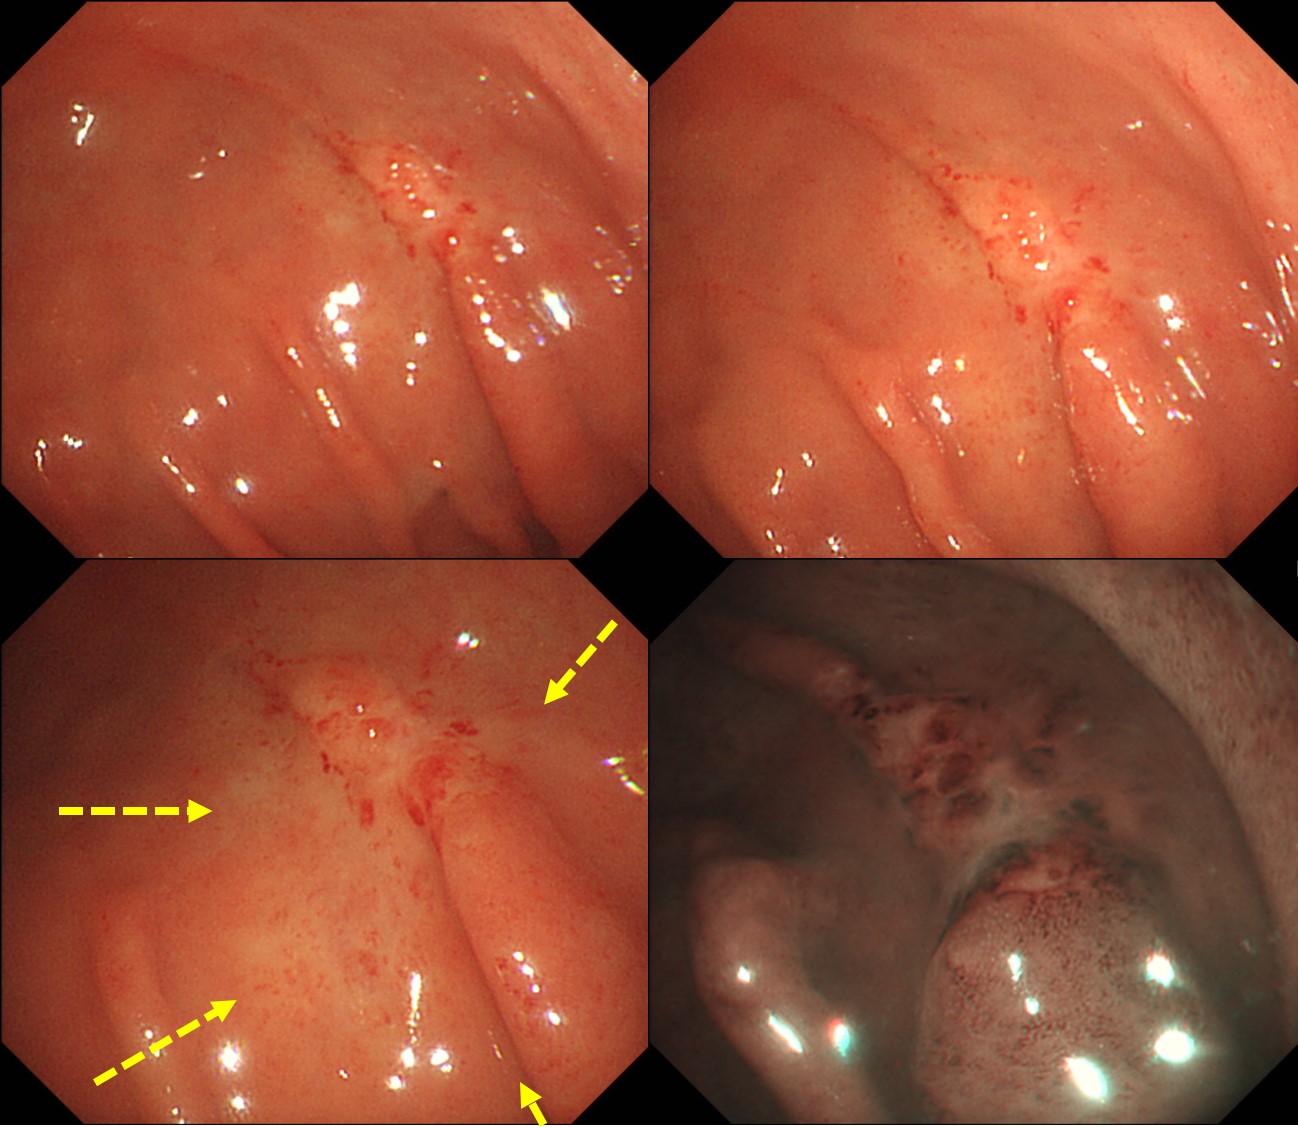

A small EGC-like lesion was found in the fundus. Biopsy was signet ring cell carcinoma

Surgery was done and the final pathology was AGC. So, it is a case of EGC-like AGC.

Final pathological stage was Ib. Observation without adjuvant chemotherapy was recommended.